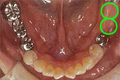

| インプラントは数本のインプラントを埋入し、そこに入れ歯を固定するため、よく噛むことができます。 |

![]() 治療前のお口の状態 |

![]() 治療前に使用中の入れ歯 |

![]() 下顎にインプラント植立し、安定装置をつけた状態 |

![]() 安定装置をつけた新しい入れ歯の内面 |

![]() 治療後の動かないでしっかりと安定した入れ歯 |